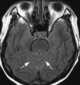

Carcinomatous infiltration

Leptomeningeal cancer (also called leptomeningeal carcinomatosis, leptomeningeal disease (LMD), leptomeningeal metastasis, neoplastic meningitis, meningeal metastasis and meningeal carcinomatosis) is a rare complication of cancer in which the disease spreads from the original tumor site to the meninges surrounding the brain and spinal cord. This leads to an inflammatory response, hence the alternative names neoplastic meningitis (NM), malignant meningitis, or carcinomatous meningitis. [Source: Wikipedia ]